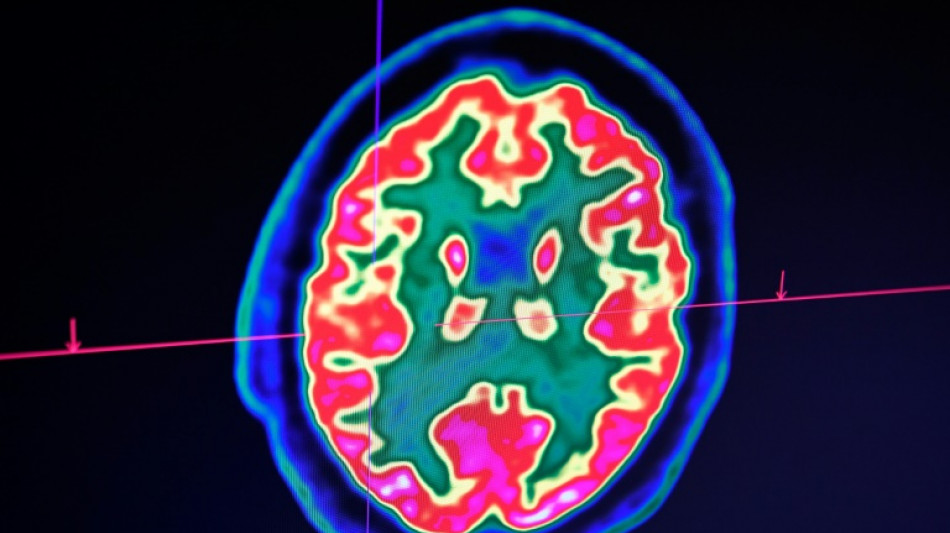

Sclérose en plaques: la découverte d'un lien avec un virus fait espérer une meilleure riposte

La découverte récente d'un lien entre la sclérose en plaques et le virus d'Epstein-Barr fait espérer une meilleure riposte à terme face à cette maladie, soulignent des spécialistes de la sclérose en plaques avant la journée mondiale de cette maladie, lundi.

Celle-ci est une maladie auto-immune du système nerveux central (cerveau et moelle épinière). Elle provoque un dérèglement du système immunitaire, qui s'attaque à la myéline, la gaine protectrice des fibres nerveuses.